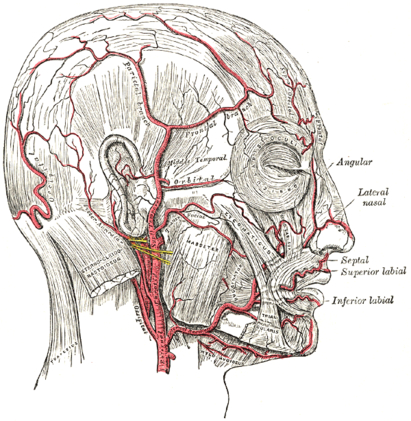

https://ru.wikipedia.org/wiki/Задняя_ушная_артерия

Выглядит это примерно так:

Учтите, что во-первых, сосуды расположены всегда индивидуально и чем они мельче, тем более рандомно, а во-вторых, сеть сосудов здесь изображена условно и, на самом деле, выглядит как-то так:

Это, ИМХО, основной фактор облысения, а вовсе не дигидротестостерон. Хотя, напоминаю, я не доктор.